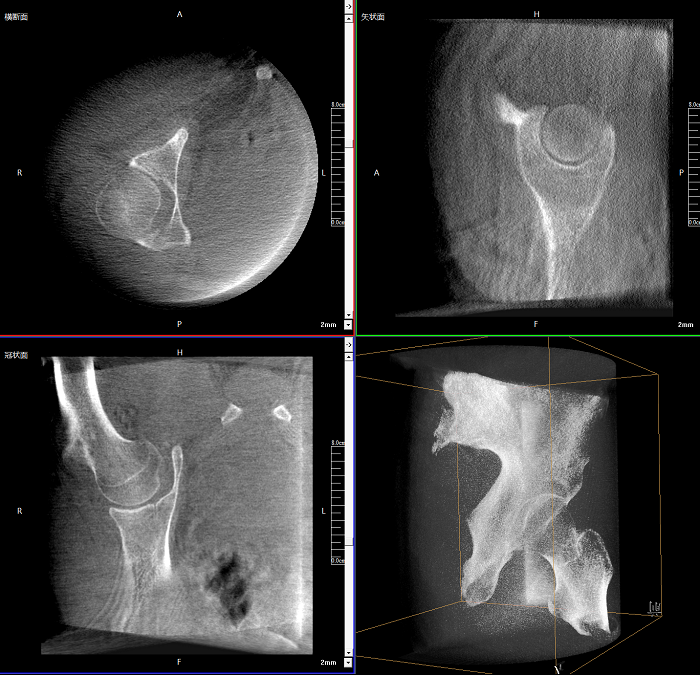

三維成像 全面觀察

任意視角、任意切面觀察

術中實時生成橫斷面、矢狀面、冠狀面及三維影像,可在任意切面、任意角度評估植入物和解剖結構的相對位置。

術中CT檢查 減少翻修概率

通過術中三維影像的檢查,可以立即發現植入物的錯位,減少不必要的第二次手術,減少并發癥概率以及感染風險。